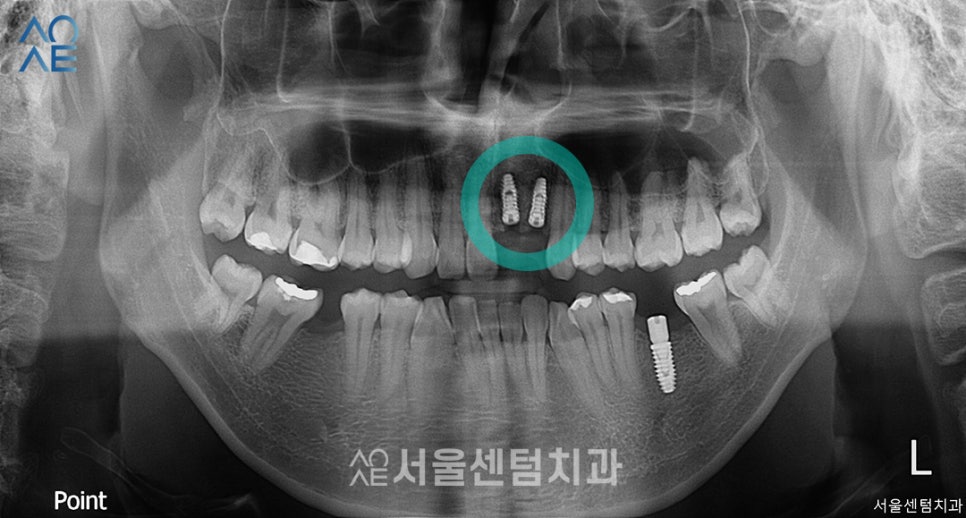

첫 치료로부터 3주 후 앞니 수술도 했습니다.

환자분이 제일 걱정했던 부분이었는데요.

일상생활에서 잘 보이는 부분이고

2개를 진행할 예정이라 많이 긴장하셨습니다.

하지만 두번째 수술이기 때문에

저희 의료진을 믿고 잘 따라와주셨습니다^^

앞니도 뼈이식을 함께 진행하였고

보철물은 5개월 뒤에 수복하기로 했습니다.

더 세심하고 정밀하게 진행하기 위해

어금니보다 더 시간을 가지기로 했습니다.